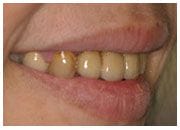

植牙過程

治療前